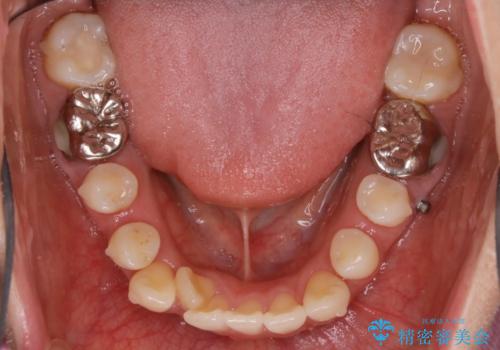

【非抜歯】インビザライン 隠れた前歯を並べる矯正治療

遠心移動

非抜歯で矯正を行う場合にガタつきの改善に必要なスペースを作るために歯の遠心移動を行います。

最初の位置から奥に歯を移動させていくことで前歯のガタつきを改善したり、前歯の位置を後方に移動させることが可能となります。

その反面、歯の移動距離が大きくなるので治療期間が長くなる傾向があり、その分コントロールの難しさが上がることが予想されます。